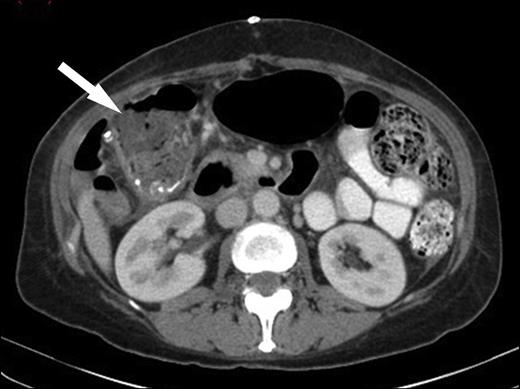

Her chest x-ray showed blunting of the left costophrenic angle and her abdominal x-ray showed multiple dilated small bowel loops with faecal loading in the descending colon. She was started on intravenous Tazobactam and Piperacillin and a CT scan of her abdomen and pelvis was performed. This showed a low attenuation lesion in the left lobe of the liver with surrounding inflammation consistent with a liver abscess (Figure 1), as well as wall thickening in the ascending colon that extended into the caecum and terminal ileum (Figure 2).

CT image demonstrating low attenuation lesion in the left lobe of the liver with surrounding inflammation consistent with a liver abscess